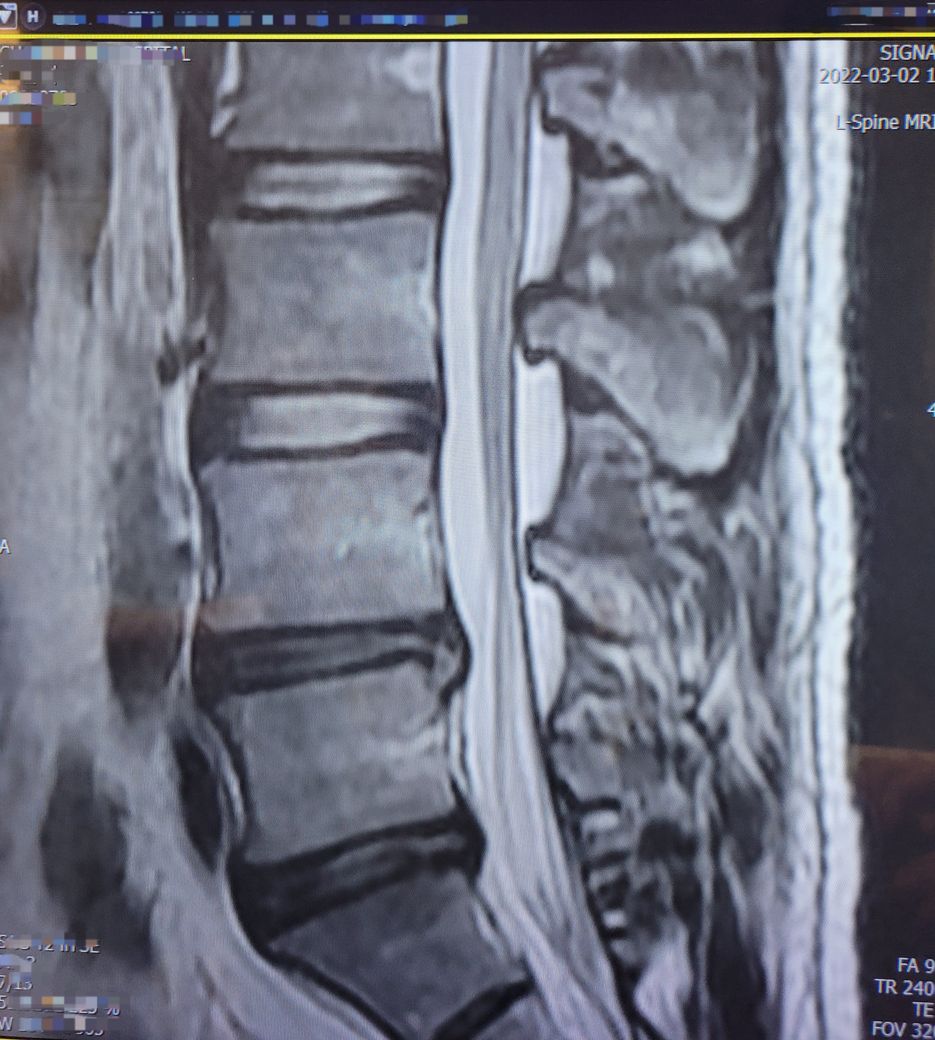

Sagital section 을 보았을 때에는 L2,3,4,5 가 모두 조금씩 눌려 있는데 이 중 L4-5, L5-S1 이 가장

많이 눌린 것으로 보입니다. 이 중 L5-S1 은 50% 이상 눌린 것으로 보이며 보통 수술결정은 추간판 수핵의

터진 상태에 따라 결정되며, 터진 추간판 수핵이 신경에 눌러 붙어 박리된 경우에는 반드시 수술이 필요하게

됩니다. 이때는 근력저하,하반신 마비와 함께 대소변에 장애, 발목에 힘이 들어가지 않아 밑으로 처지는 풋드랍

현상이 나타 나는데 이러한 증상이 나타날 때는 정확한 진단 후 수술적 치료가 필요합니다. 감사합니다.